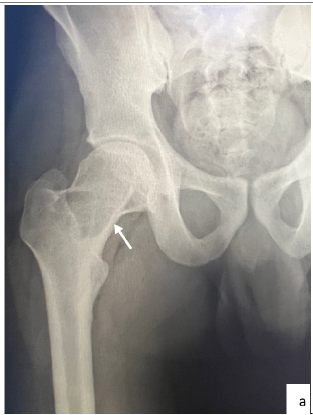

Aneurysmal Bone Cyst in an Adult Patient Located in the Femoral Head and Neck; Positive and Differential Diagnosis

Andour Hajar, Zaizi Abderahim, Ben El Hend Salah, Fikri Abdelghani. 13(12): 28-32.